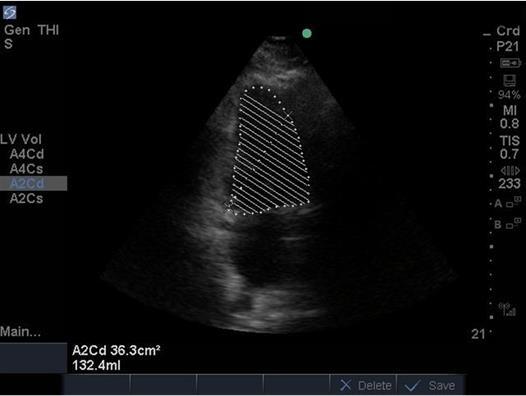

Heart Ejection Fraction (EF) 4 Image